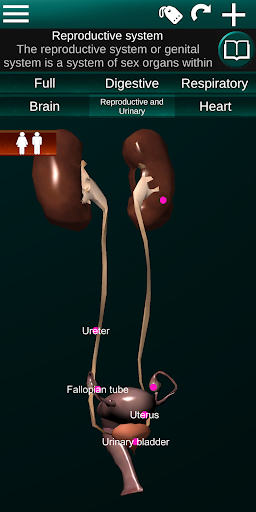

Internal Organs in 3D Anatomy لـ Vodafone Smart N9 Lite

(الأجهزة الداخلية في)

Internal Organs 3D Anatomy 3.4

يمكنك هنا تنزيل ملف حزمة تطبيق أندرويد "Internal Organs 3D Anatomy" الخاصة بجهازVodafone Smart N9 Lite مجانًا، نسخة ملف حزمة تطبيق أندرويد - 3.4 للتحميل على Vodafone Smart N9 Lite اضغط ببساطة على هذا الزر. إنه سهل وآمن. نحن نقدم فقط ملفات حزمة تطبيق أندرويد الأصلية. إذا انتهكت أية مواد موجودة في الموقع حقوقك قم بإبلاغنا من خلال